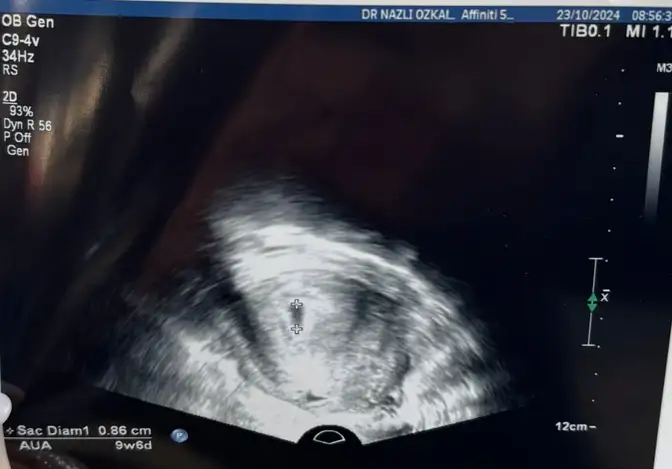

Bebeklerim çıktım üniversite tarafına eltimin yanına geldim sonuçlar harika kalp atışı müthiş ve ilginç şekilde çok fazla hareketli kocaman olmuş minik tırtıl

Ya minnoşum benim çok tatlısınız minnak bir kese birden bire nasıl büyüyor inanılmaz benim doktor bile şok oldu biliyor musun bu kadar büyümesine üstteki fotoğrafta direk bebeği bile görebilirsiniz kan akışı falan da çok hareketli on gün içerisinde minicik kurtçuk insana dönüşmüş şaka gibi

Kız sorma aşkım ya kan akışı da kendi de çok hareketli bildiğin yüzüyordu suyun içinde sanki videomu atabilsem buraya keşke o sesini duydum ya dünyalar benim oldu resmen kız bildiğin tak tak tak tak tak atıyor